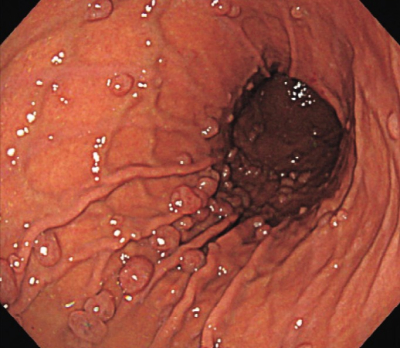

40歳の女性。人間ドックの上部消化管造影検査で胃に異常を指摘されたため来院した。上部消化管内視鏡像を示す。

対応として適切なのはどれか。